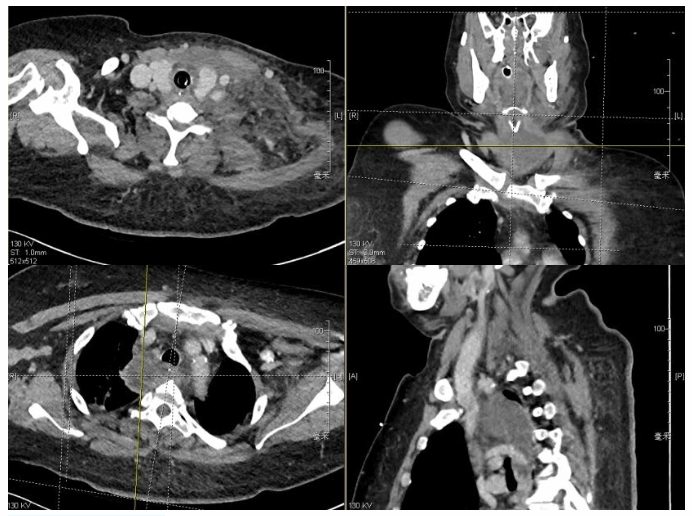

耳鼻喉科急诊为李女士完善了相关化验及检查后,诊断为颈深部脓肿,而且颈部的感染顺着气管周围间隙直达上纵隔,形成了下行性纵隔脓肿。

患者CT显示颈深部脓肿

因为合并了糖尿病酮症、肺炎、高血压等疾病,如果感染得不到有效控制,李女士很可能会出现脓毒血症、感染中毒性休克等致死性并发症,随时危及生命。此外,严重的脓肿已经引起了急性呼吸窘迫综合征(ARDS),情况紧急,耳鼻喉科进行了气管插管后,李女士转入危重医学科进一步治疗。